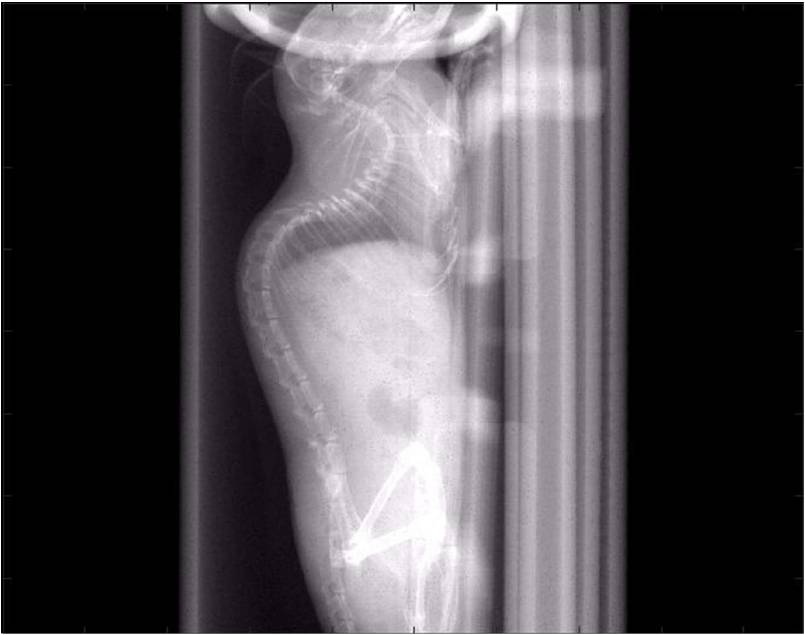

小鼠X光.jpg

• 一鍵自動(dòng)辨識載床并快速設定

• 選擇濾鏡與FOV模式

• 掃描時(shí)間:2秒(高速模式)

• 2μm高分辨率影像

• 專(zhuān)利的載床設計可自動(dòng)辨識、防撞

• 獨立的熱風(fēng)系統與氣體麻醉,穩定動(dòng)物生命征象

• 配置球管能量范圍:40-90 kVp, 50W高能量電源